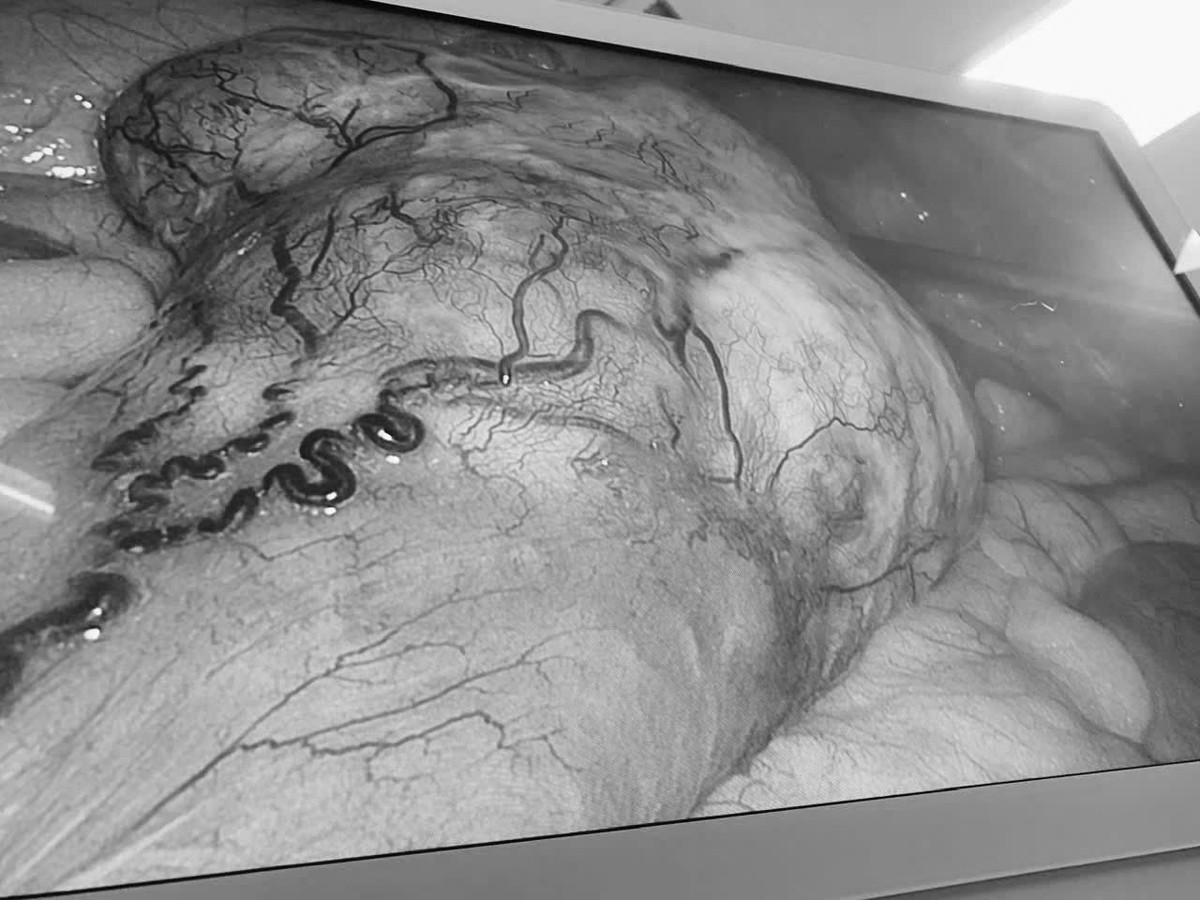

Hình ảnh khối u được quan sát rõ qua nội soi trong quá trình phẫu thuật, giúp bác sĩ đánh giá chính xác vị trí và mức độ tổn thương. Ảnh BV

Theo ThS.BS.CKI Trần Nhật Phi, phẫu thuật viên trực tiếp thực hiện ca mổ cho bệnh nhân N.T.N. chia sẻ: “Việc phẫu thuật cho bệnh nhân mang đồng thời hai khối u ở hai vị trí khác nhau là một thách thức lớn. Thời gian mổ kéo dài, nguy cơ biến chứng tăng cao và luôn tiềm ẩn khả năng phải chuyển sang phẫu thuật mở nếu không kiểm soát tốt các tình huống phát sinh trong quá trình can thiệp”.

Theo bác sĩ, những khó khăn chính đặt ra trong ca phẫu thuật bao gồm việc phải phẫu tích đồng thời ở hai vùng giải phẫu khác nhau, vừa đảm bảo nguyên tắc ung thư học trong điều trị ung thư đại tràng, vừa kiểm soát tốt tình trạng chảy máu, bảo tồn tối đa các cấu trúc lành, đồng thời đảm bảo an toàn gây mê trong suốt thời gian phẫu thuật kéo dài.

Sau 180 phút can thiệp, hai khối u đã được cắt bỏ hoàn toàn mà không cần chuyển sang phẫu thuật mở. Ca mổ đảm bảo các nguyên tắc ung thư học, trong đó khối u đại tràng được cắt triệt căn, khối u ruột non nghi GIST được lấy trọn, không làm vỡ bao u. Lượng máu mất trong quá trình phẫu thuật ước tính khoảng 100 ml.